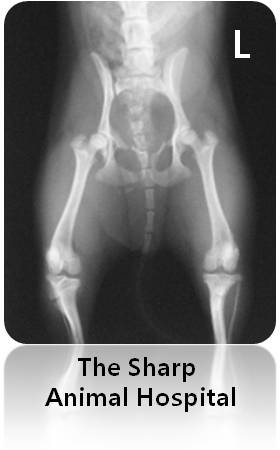

일반 깁스를 하고 2주후 다시 엑스레이 촬영을 하게 되었습니다.

물런 그 동안 럭쭈리가 가만히 있지 않았다고 하시더라고요...  ^^;;

붕대를 다 풀어 헤치고...  ㅠ.ㅜ

그래도 다행스럽게 뼈는 유합이 되어 가고 있는 중이었습니다.